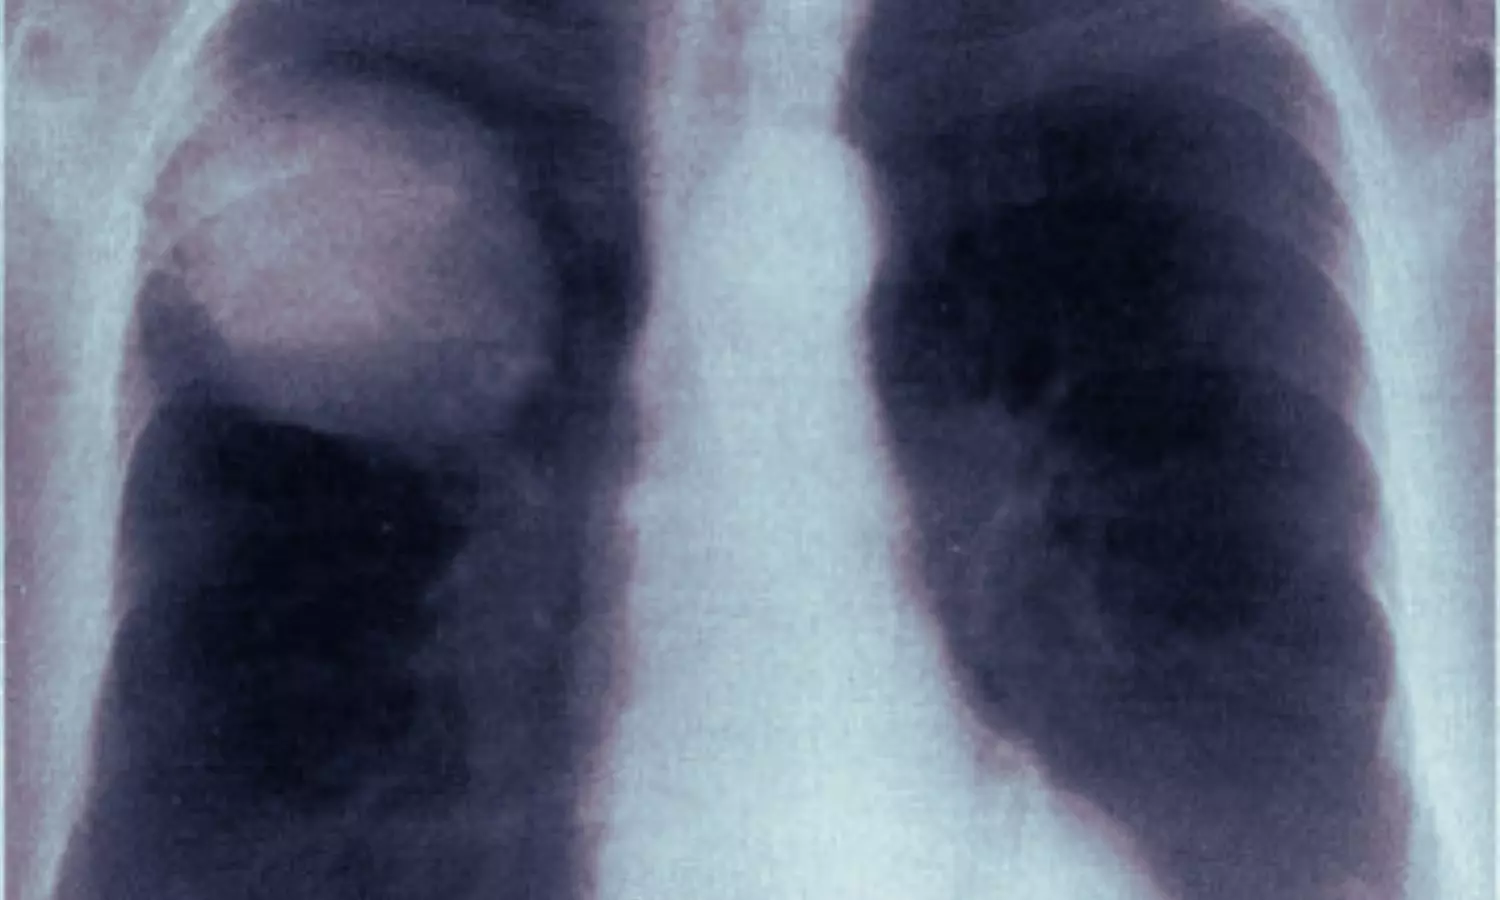

The case involved a 52-year-old male who underwent dual-port VATS for right upper lobectomy and right lower lobe superior segmentectomy to treat invasive pulmonary adenocarcinoma. On the second postoperative day, just two hours after chest tube removal, the patient experienced a sudden onset of profuse sweating, chest tightness, and difficulty breathing. Emergency chest X-rays showed complete lung atelectasis, and subsequent multidetector CT scans with flexible bronchoscopy confirmed incomplete torsion affecting the right middle and lower lobes.